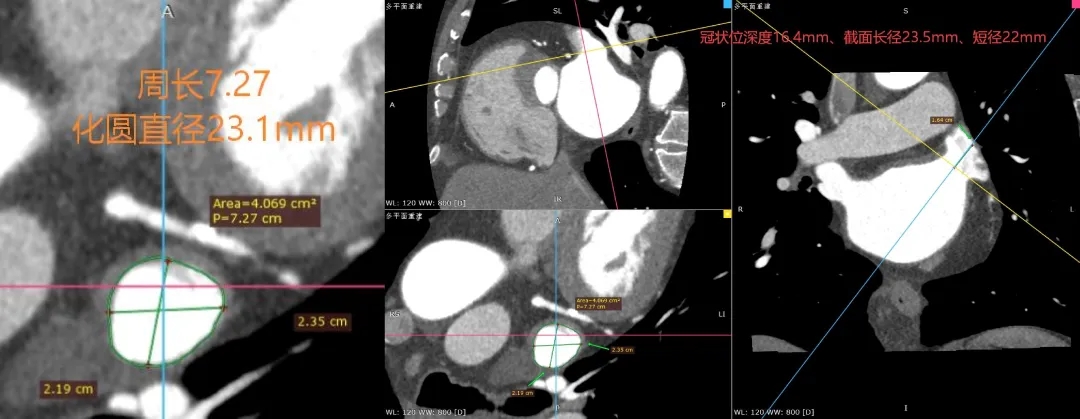

术前CT测量图

左心耳开口近圆形,MPR周长72.7mm,化圆直径23.1mm。